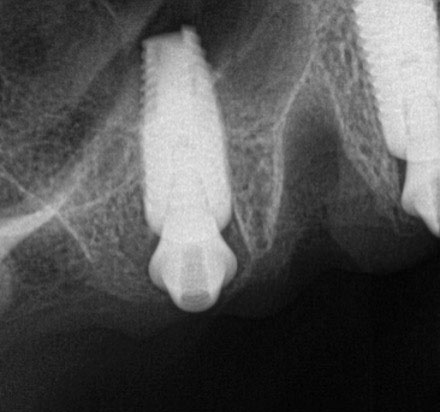

Postoperative x-rays documented the full seating of the prosthesis on the multi-unit abutments (Figure 21 and Figure 22). The patient returned at 1 week postoperatively for a follow-up visit and to review home care. She remarked that the restoration was comfortable and that she was free of discomfort and extremely pleased with the makeover she received in one day.

Fig 21. Postoperative panoramic radiograph on the day of surgery.

Figure 21

Fig 22. Postoperative periapical x-rays on the day of surgery demonstrating the provisional restoration with ti-bases fully seated to multi-unit abutments and ideal immediate implant placement.

Figure 22